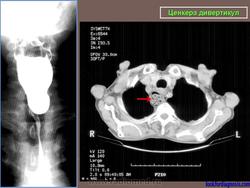

Ценкера дивертикул.

Barium swallow with fluoroscopy, lateral view</p> <p>During swallowing an outpouching of the posterior hypopharyngeal wall is clearly visualised at the level C5-C6, right above the upper oesophageal sphincter. The pouch is characterized by a narrow neck entrapping some barium after the swallowing.

ID: 12377 Zenker's diverticulum Dr Erik Ranschaert - 18 Nov 2010 Zenker's diverticulum

Случай 2: осевой КТ